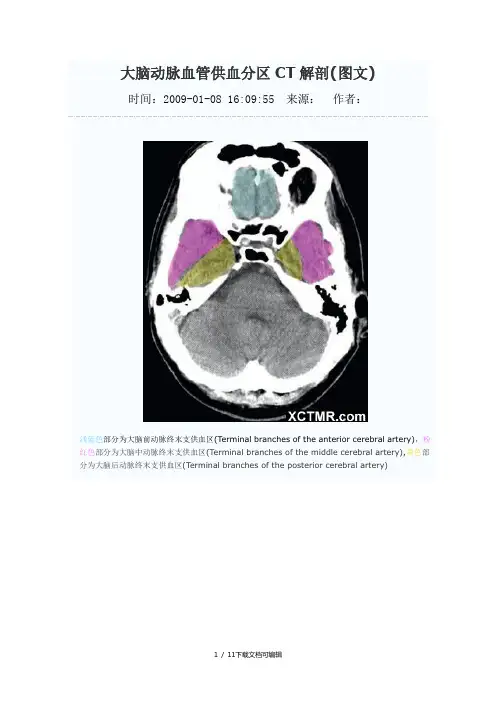

大脑动脉血管供血分区CT解剖(图文)时间:2009-01-08 16:09:55 来源:作者:浅蓝色部分为大脑前动脉终末支供血区(Terminal branches of the anterior cerebral artery),粉红色部分为大脑中动脉终末支供血区(Terminal branches of the middle cerebral artery),黄色部分为大脑后动脉终末支供血区(Terminal branches of the posterior cerebral artery)浅蓝色部分为大脑前动脉终末支供血区(Terminal branches of the anterior cerebral artery),粉红色部分为大脑中动脉终末支供血区(Terminal branches of the middle cerebral artery),黄色部分为大脑后动脉终末支供血区(Terminal branches of the posterior cerebral artery),绿色部分为脉络膜前动脉供血区(Anterior choroidal artery),浅蓝色部分为大脑前动脉终末支供血区(Terminal branches of the anterior cerebral artery),粉红色部分为大脑中动脉终末支供血区(Terminal branches of the middle cerebral artery),黄色部分为大脑后动脉终末支供血区(Terminal branches of the posterior cerebral artery),绿色部分为脉络膜前动脉供血区(Anterior choroidal artery),褐色部分为大脑前动脉深穿支供血区(Penetrating branches of the anterior cerebral artery),枣红色部分为大脑后动脉深穿支及后交通动脉供血区(Penetrating branches of the posterior cerebral artery and posterior communicating artery),浅蓝色部分为大脑前动脉终末支供血区(Terminal branches of the anterior cerebral artery),粉红色部分为大脑中动脉终末支供血区(Terminal branches of the middle cerebral artery),黄色部分为大脑后动脉终末支供血区(Terminal branches of the posterior cerebral artery),绿色部分为脉络膜前动脉供血区(Anterior choroidal artery),褐色部分为大脑前动脉深穿支供血区(Penetrating branches of the anterior cerebral artery),枣红色部分为大脑后动脉深穿支及后交通动脉供血区(Penetrating branches of the posterior cerebral artery and posterior communicating artery),亮红色部分为大脑中动脉深穿支供血(Penetrating branches of the middle cerebral artery)浅蓝色部分为大脑前动脉终末支供血区(Terminal branches of the anterior cerebral artery),粉红色部分为大脑中动脉终末支供血区(Terminal branches of the middle cerebral artery),黄色部分为大脑后动脉终末支供血区(Terminal branches of the posterior cerebral artery),绿色部分为脉络膜前动脉供血区(Anterior choroidal artery),枣红色部分为大脑后动脉深穿支及后交通动脉供血区(Penetrating branches of the posterior cerebral artery and posterior communicating artery),亮红色部分为大脑中动脉深穿支供血(Penetrating branches of the middle cerebral artery)浅蓝色部分为大脑前动脉终末支供血区(Terminal branches of the anterior cerebral artery),粉红色部分为大脑中动脉终末支供血区(Terminal branches of the middle cerebral artery),黄色部分为大脑后动脉终末支供血区(Terminal branches of the posterior cerebral artery),枣红色部分为大脑后动脉深穿支及后交通动脉供血区(Penetrating branches of the posterior cerebral artery and posterior communicating artery),亮红色部分为大脑中动脉深穿支供血(Penetrating branches of the middle cerebral artery)浅蓝色部分为大脑前动脉终末支供血区(Terminal branches of the anterior cerebral artery),粉红色部分为大脑中动脉终末支供血区(Terminal branches of the middle cerebral artery),黄色部分为大脑后动脉终末支供血区(Terminal branches of the posterior cerebral artery),浅蓝色部分为大脑前动脉终末支供血区(Terminal branches of the anterior cerebral artery),粉红色部分为大脑中动脉终末支供血区(Terminal branches of the middle cerebral artery),黄色部分为大脑后动脉终末支供血区(Terminal branches of the posterior cerebral artery),浅蓝色部分为大脑前动脉终末支供血区(Terminal branches of the anterior cerebral artery),粉红色部分为大脑中动脉终末支供血区(Terminal branches of the middle cerebral artery),黄色部分为大脑后动脉终末支供血区(Terminal branches of the posterior cerebral artery),浅蓝色部分为大脑前动脉终末支供血区(Terminal branches of the anterior cerebral artery),粉红色部分为大脑中动脉终末支供血区(Terminal branches of the middle cerebral artery),浅蓝色部分为大脑前动脉终末支供血区(Terminal branches of the anterior cerebral artery)(学习的目的是增长知识,提高能力,相信一分耕耘一分收获,努力就一定可以获得应有的回报)11 / 11下载文档可编辑。